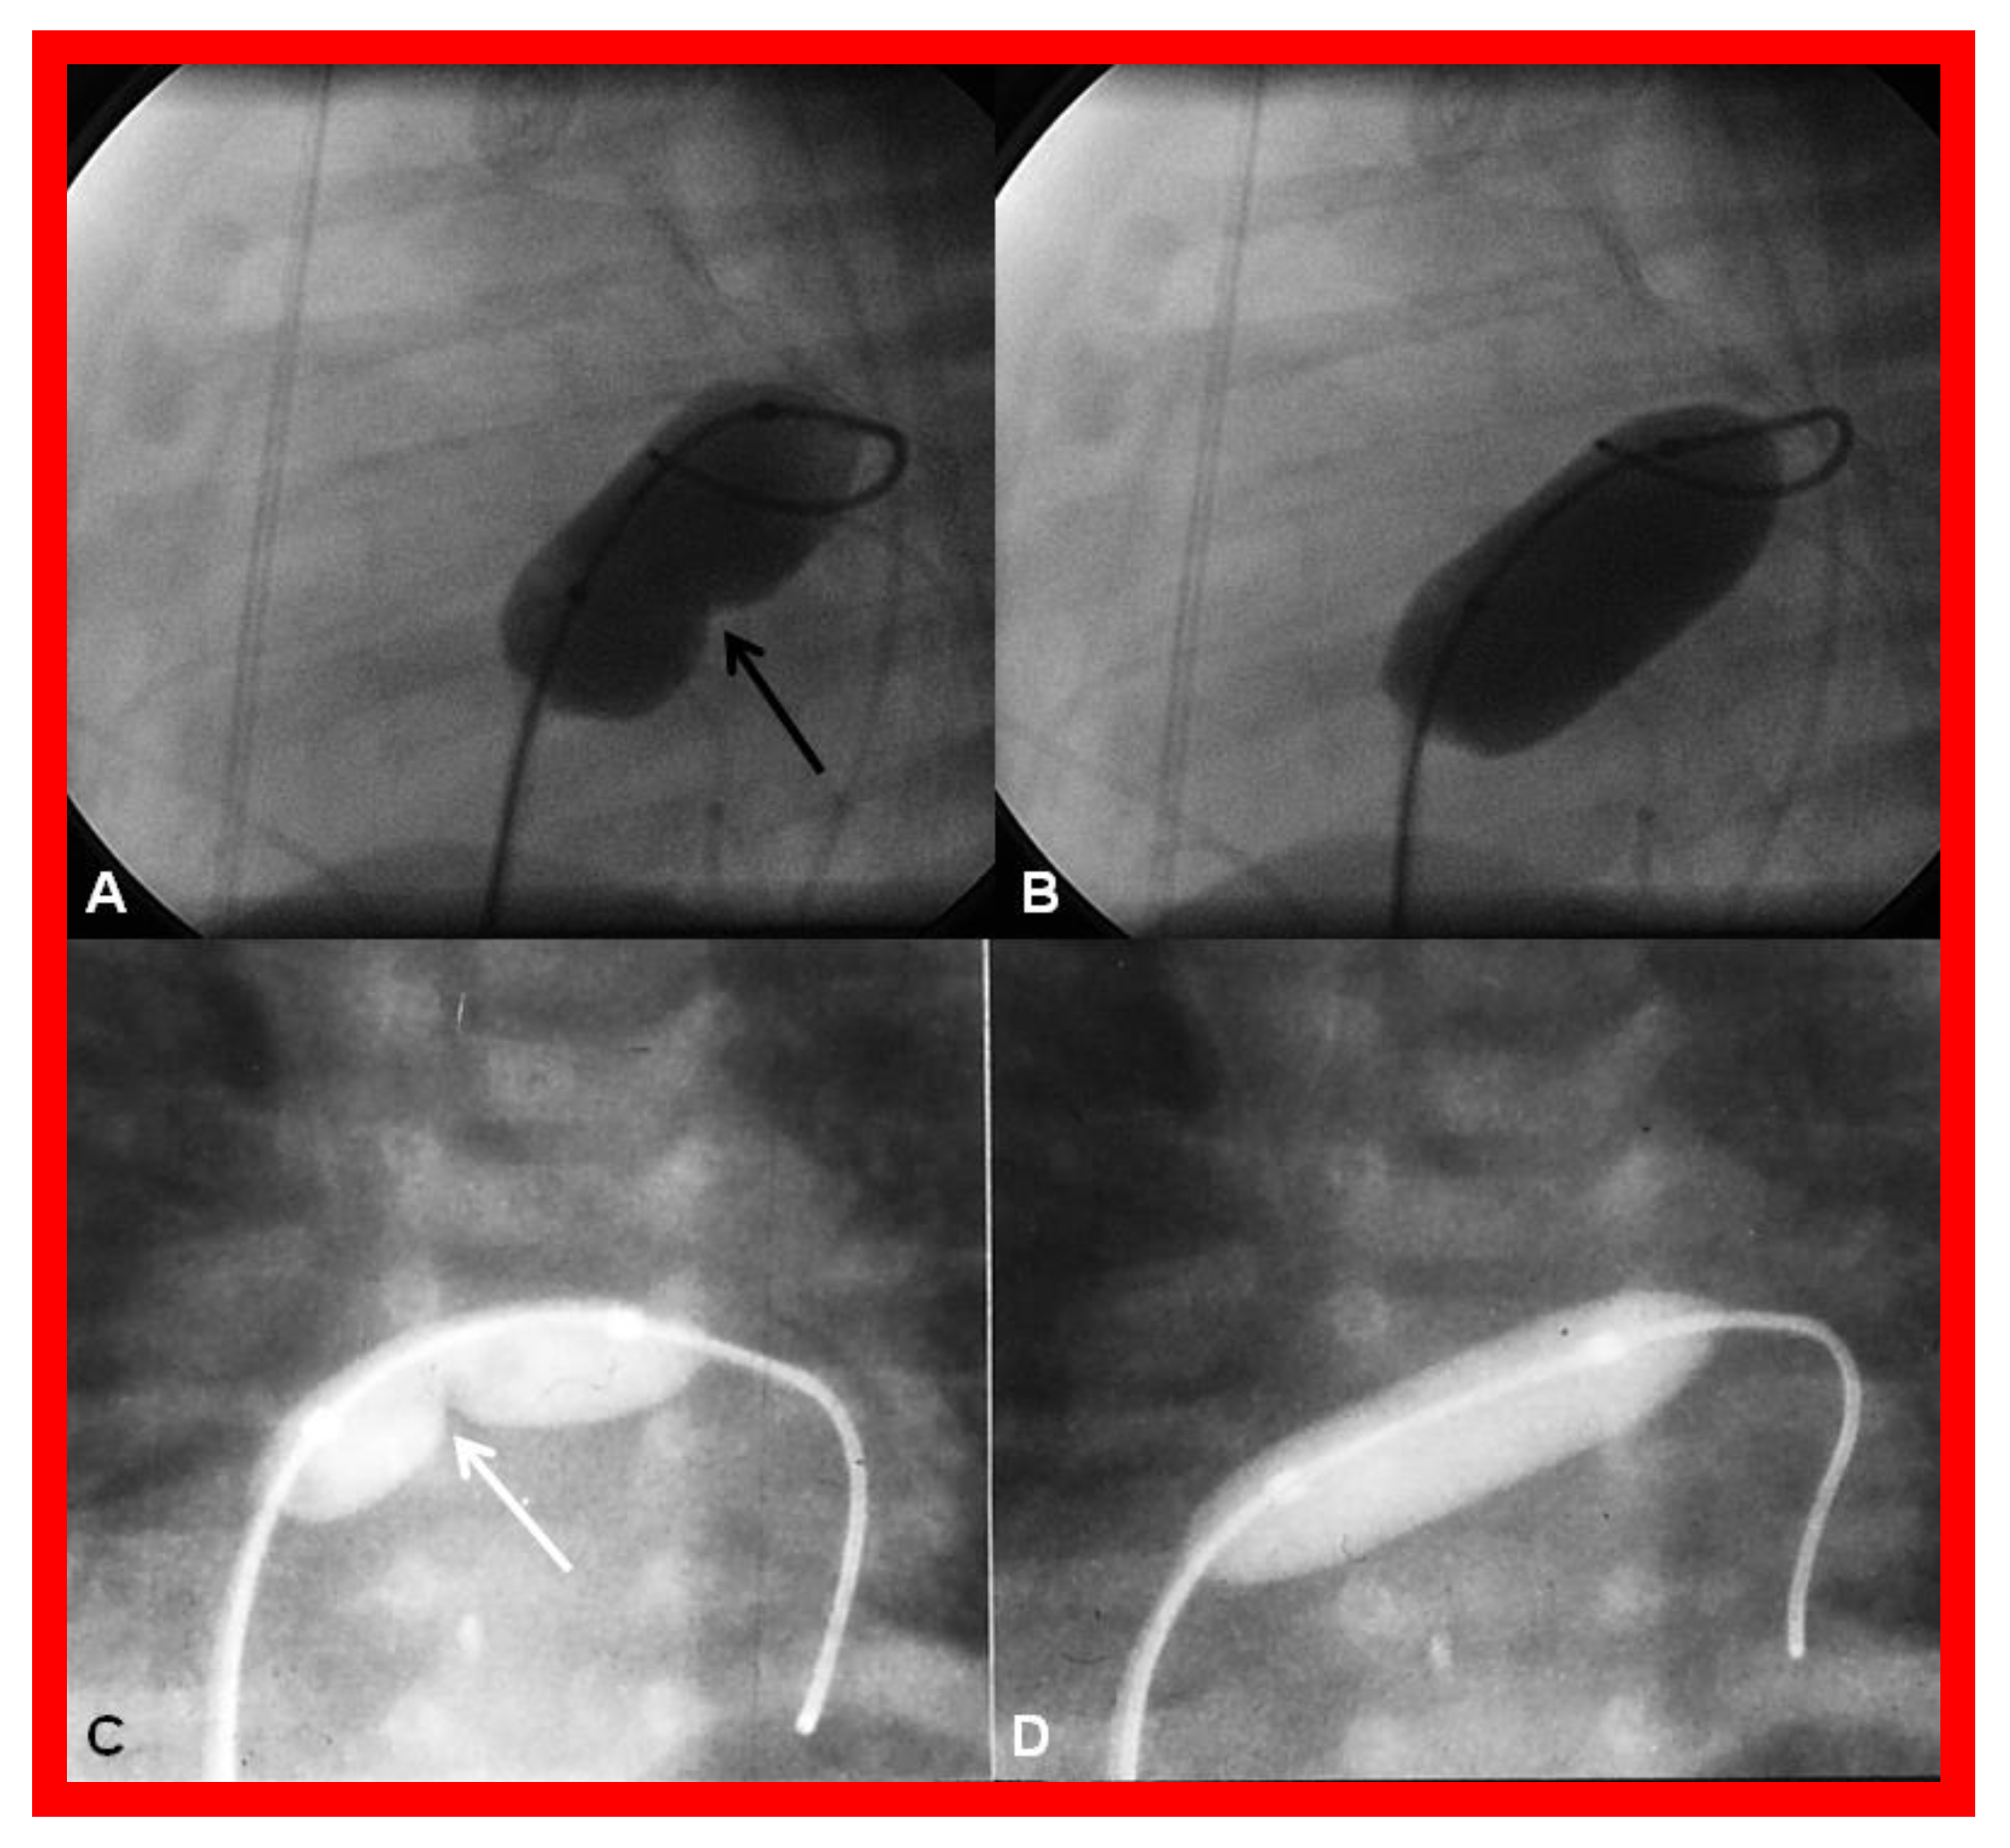

4.3.2. Stage IIIB

During the Stage IIIB, the fenestration is occluded (Figure 17) by transcatheter methods [33,81,83,84,85], usually 6–12 months following Stage IIIA Fontan. In the past, all previously available ASD occluding devices [81,83,84,85] were used for fenestration closure. However, at the present time, Amplatzer Septal Occluders are the most regularly used devices to accomplish fenestration closures. Any other residual shunts may also be addressed by device closure.

Figure 17.

(a). Cineangiogram in antero-posterior view, illustrating Stage IIIA of the Fontan operation, diverting the inferior vena caval (IVC) blood flow into the pulmonary arteries via a non-valve conduit (Cond). Fenestration (Fen) is shown by the arrow in (a). The Fen is occluded with an Amplatzer device (D), shown by the arrow in (b) (Stage IIIB). HV, hepatic veins; LPA, left pulmonary artery; RPA, right pulmonary artery. Reproduced from Reference [33].